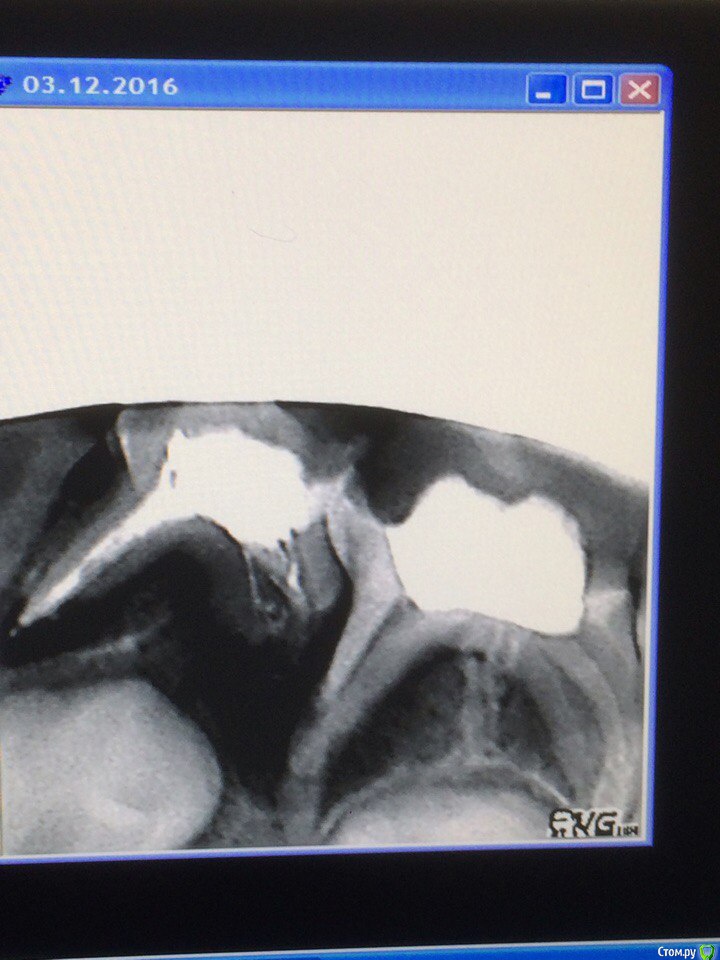

сирена Опубликовано 19 января, 2017 Поделиться Опубликовано 19 января, 2017 (изменено) И я тут спрошу с разрешения ТС.Удалять или лечить?У меня постоянные конфликты с терапевтами по этому вопросу.Я настаиваю на Лечить,они - на удалять(работаю в детской поликлинике хирургом).Основание к удалению:"1,5 - 2 года до физсмены".У Рабиновича это показание к удалению.Я в недоуменииРебёнку 7 лет. Изменено 19 января, 2017 пользователем сирена Ссылка на комментарий

Джима Опубликовано 19 января, 2017 Поделиться Опубликовано 19 января, 2017 Ну конкретно здесь вообще пульпит, по-моему, можно ампутационно лечить. Пожуёт ещё, 2 года - это четверть жизни в восьмилетнем возрасте, если что. Может, я там чего не рассмотрела?..Ху из Рабинович, какого года? Если это рекомендации для советской системы санации дет.населения, так они работали на благо массам в ущерб отдельным детёнышам. 2 Ссылка на комментарий

Большой Зеленый Опубликовано 20 января, 2017 Поделиться Опубликовано 20 января, 2017 И я тут спрошу с разрешения ТС.Удалять или лечить?У меня постоянные конфликты с терапевтами по этому вопросу.Я настаиваю на Лечить,они - на удалять(работаю в детской поликлинике хирургом).Основание к удалению:"1,5 - 2 года до физсмены".У Рабиновича это показание к удалению.Я в недоумении20170117_225011-1.jpgРебёнку 7 лет.Если это пульпит то однозначно лечить. Если же это периодонтит то удаляем.. 1 Ссылка на комментарий

Redrum Опубликовано 20 января, 2017 Поделиться Опубликовано 20 января, 2017 Дело не в том,сколько ребенку лет,а в том, насколько далеко до смены. Буквально неделю назад сделали ОПТГ мальчику 7 лет, активно рассасываются корни всех "пятерок", "четвертые" уже сменились. А несколько дней назад лечу пульпит в зубе 84,потому как во-первых болит,а во-вторых,по результатам ОПТГ до смены еще очень долго. 2 Ссылка на комментарий

red_butler Опубликовано 30 января, 2017 Поделиться Опубликовано 30 января, 2017 Я настаиваю на Лечить,они - на удалять(работаю в детской поликлинике хирургом)когда я детской хирургией баловался, было все наоборот Но то что на снимке, нужно лечить 1 Ссылка на комментарий